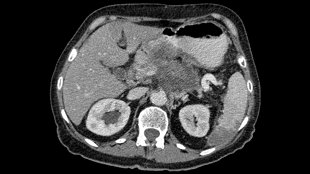

胰腺癌,圖片來自維基共享資源|Hekkerhoff

來自英國劍橋大學腫瘤研究所(Cancer Research UK Cambridge Research Institute)的David Tuveson和他的同事們注意到胰腺癌(pancreatic cancer)細胞似乎特別能夠抵抗脅迫應激,并且追蹤這種強有力的抵抗性后發現是因為胰腺癌細胞相對于正常的細胞而言含有較低水平的ROS。